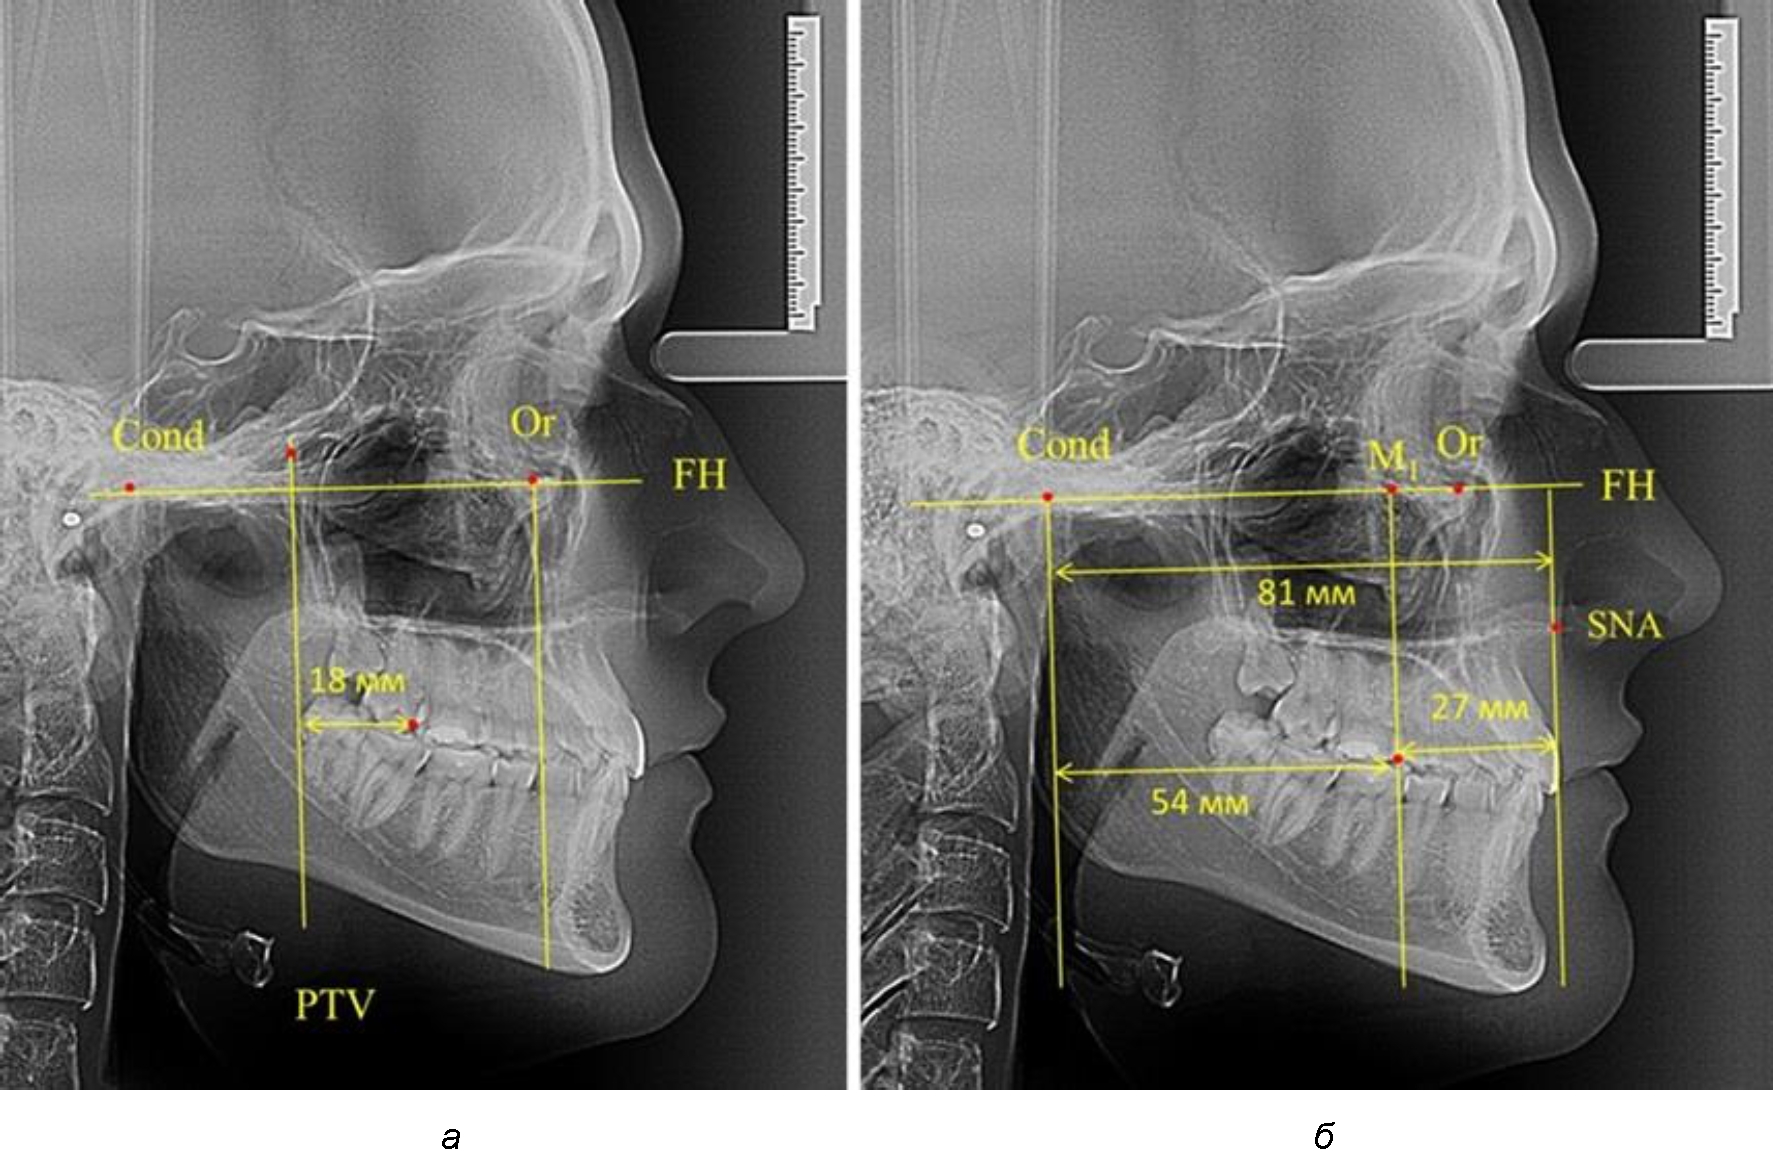

Рис. 1. Метод определения положения первых верхних моляров по Ralph E. McDonald (а) и по предложенному методу (б)

Анализ проведенного исследования рентгенограмм показал существенную вариабельность практически всех линейных показателей. У молодых людей с физиологическим прикусом постоянных зубов расстояние от крыловидной вертикальной плоскости PTV до дистальной поверхности верхнего первого постоянного моляра в целом по группе составляло (18,37 ± 3,62) мм. Обращает на себя внимание большая ошибка репрезентативности из-за разницы между максимальными и минимальными значениями.

Среди анализируемых рентгенограмм минимальное значение расстояния по методу R. E. McDonald было 12 мм, а максимальное достигало 25 мм, что, по нашему мнению, обусловлено вариабельностью сагиттального размера гнатического отдела лица.

Таким образом, для прогнозирования оптимального положения первых постоянных моляров наиболее целесообразным методом явилось использование относительного показателя, что подтверждено при анализе рентгенограмм с минимальными и максимальными значениями по методу R. E. McDonald.

Так, при расстоянии от крыловидной вертикальной плоскости PTV до дистальной поверхности верхнего первого постоянного моляра в 13 мм сагиттальный размер гнатического отдела был 82 мм. При этом отношение кондилярно-спинального расстояния к кондилярно-молярному размеру (54,5) было близким к коэффициенту 1,5, что представлено на рис. 2.